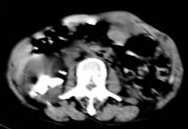

标题: CT2840:腹部占位,请会诊? [打印本页]

标题: CT2840:腹部占位,请会诊?

男,66岁,上腹部胀疼,无其他不适.

1胆管细胞癌

2右肾囊肿

考虑胆管细胞型肝癌可能性大,右肾囊肿,左肾结石

考虑胆管细胞型肝癌可能性大,胆结石,双肾结石。肝、肾血管平滑肌脂肪瘤不除外。

双肾结石,胆结石,肝内胆管扩张,肝左叶占位病变,请做增强ct.

考虑肝、肾血管平滑肌脂肪瘤可能,肾结石,右肾积水。

肝胆管细胞癌,右肾积水

考虑胆管细胞型肝癌可能性大,胆结石,双肾结石。右肾积水。 建议增强扫描及复部肠道准备

肝左叶胆管细胞癌,胆囊结石,双肾结石,右肾积水。

胃肠道恶性肿瘤伴肝脏转移,腹膜转移。

右肾结石,囊肿。

肾脏的结石中肾盂叫结石,在肾实质叫钙化。肝左叶胆管细胞癌可能,钙胆汁,右肾结石,左肾实质钙化